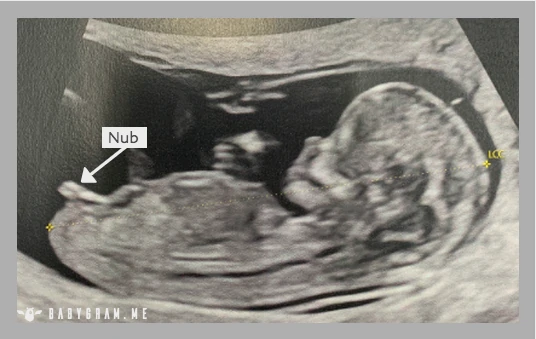

The nub theory is a medical method used by professional healthcare physicians to get an early prediction of your baby's gender from an ultrasound. The term nub theory came from the analysis of the "Nub." A Nub is also known as a genital tubercle, i.e., your child's indeterminate sexual organ.

Are you wondering how you can tell if it is a boy or a girl in a scan? The answer is simple, i.e., a boy's Nub will be pointing out in a different direction than a girl's Nub.

If you are expecting a baby boy, the Nub will angle upwards. On the other hand, if you are going to have a girl, the Nub will lie down flatter. Hence, another un-formal yet witty term used for nub theory is "the angle of the dangle" that reveals if the fetus inside you is a boy or a girl.

The nub theory relies on analyzing the angle between your baby's spine and the Nub. Here is a short description of the variation.

- It's a boy! - if the Nub forms a 30-degree angle or more in relation to the spine.

- It's a girl! - If the Nub is pointing straight out, forming an angle under 30 degrees in relation to the spine.